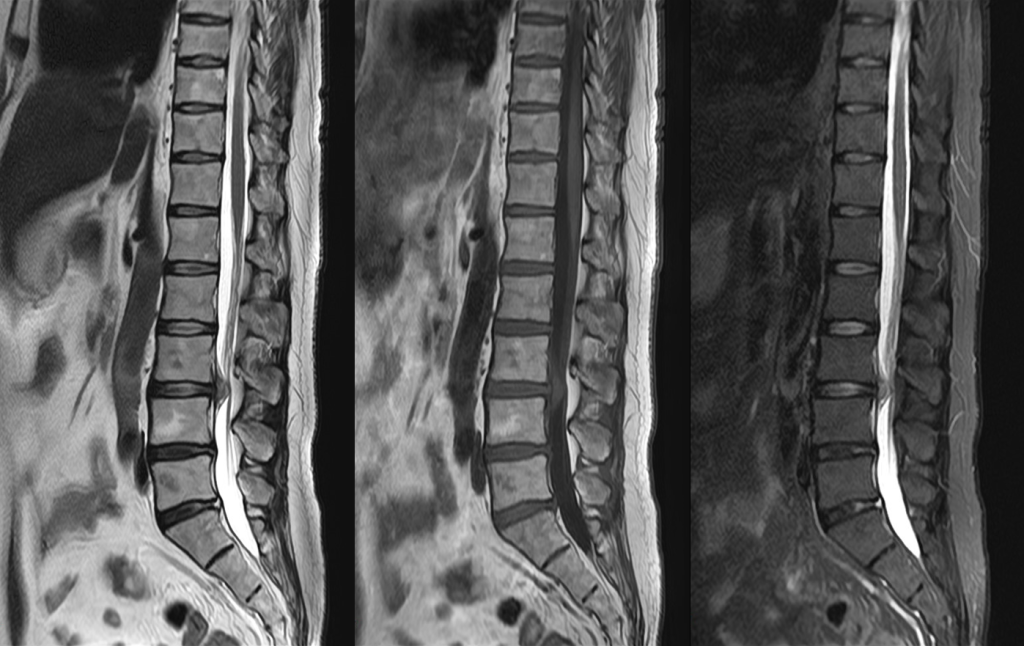

MRI

MRIとはMagnetic Resonance Imaging(磁気共鳴画像法)の略で、強力な磁石と電波を使って様々な角度から体の断面を画像化する検査です。

X線を使用しないため、放射線被ばくの心配がなく、軟部組織(筋肉、靱帯、神経など)の描出に優れており、がんの有無や広がり、転移の有無などを調べることができます。また、造影剤を用いずに血管を描出することが可能です。

当院ではCanon社製Vantage Fortian MRI 1.5Tを設置しており、主に脳血管疾患、脊椎疾患、閉塞性動脈硬化症などの下肢疾患、腹部疾患、心臓疾患、関節等の検査を行っています。